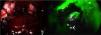

Quince días después, persiste evolución tórpida. La tomografía de control describió una colección encapsulada a nivel de la cola del páncreas y de la corredera parietocólica izquierda (fig. 1). Se decide realizar VARD. Cuarenta y cinco minutos previo a la cirugía se administraron 2.5ml de verde de indocianina diluidos en 5cc de solución salina. Se utilizó el catéter pigtail colocado en la línea axilar media izquierda 5cm superior de la espina ilíaca anterosuperior para introducir trocar de 12mm. Se realiza insuflación con CO2 hasta 12mmHg y, bajo visualización directa, se coloca un trocar de 5mm. Se aspira líquido de necrosis, obteniéndose 600cc de líquido purulento. Con ayuda de verde de indocianina se realizó desbridamiento del tejido desvitalizado, evitando el daño a estructuras vasculares y al conducto pancreático principal. Se realizó el lavado de cavidad con suero fisiológico y se retiró el catéter pigtail, colocándose un drenaje cerrado tipo Blake de 25FR (fig. 2).